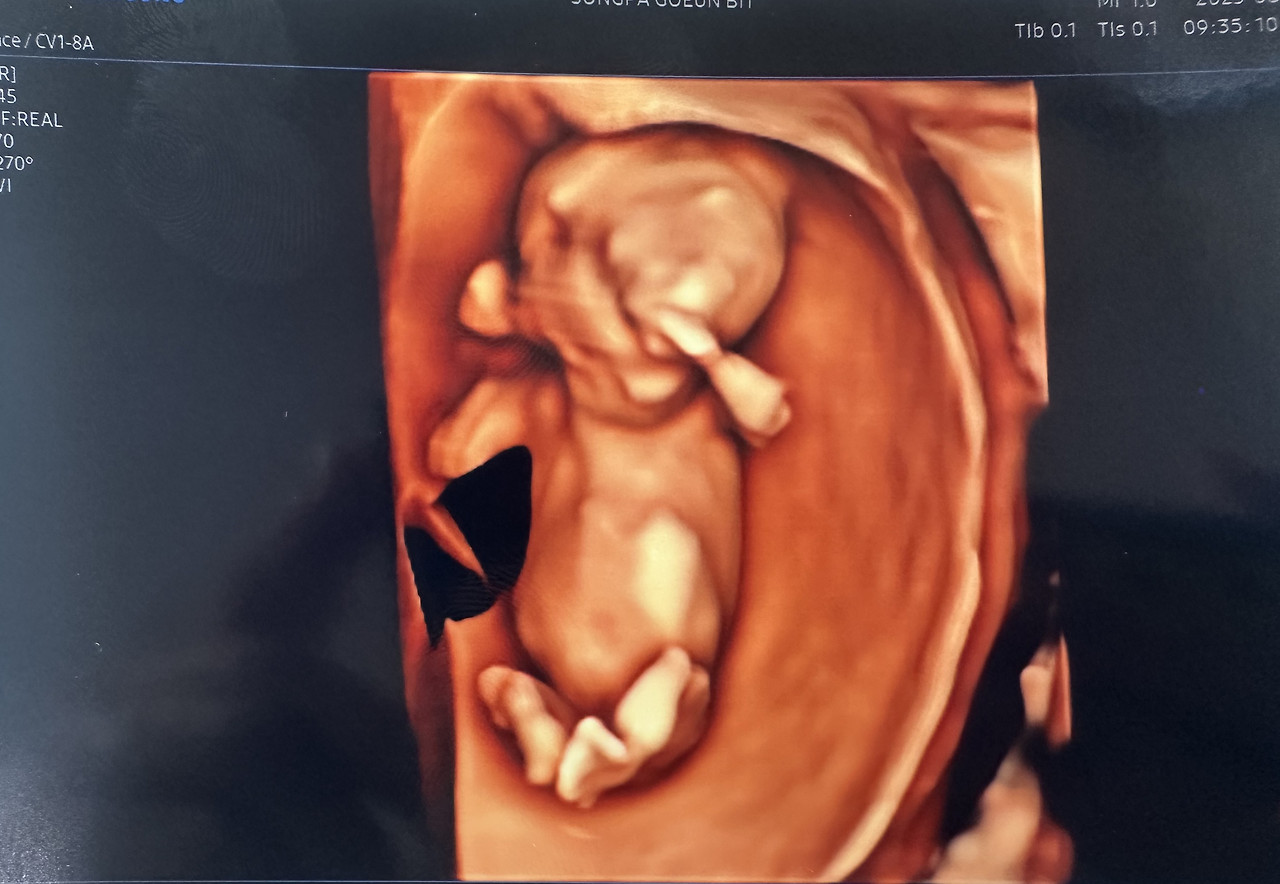

예약해 둔 정밀 초음파는 정확한 시간에 시작되었다.

7분 남짓의 시간 동안, 내 손바닥보다 작은 생명이 화면 속에서 움직이고 있었다.

불과 12cm 남짓한 몸인데, 손과 발, 머리, 엉덩이까지 모두 자리 잡고 있었다.

입체 초음파 화면 속 아이는 작은 손을 머리 위로 올리고 있었다.

선생님은 “손을 머리에 얹고 있네요.”라고 설명했지만,

내 눈에는 마치 ‘경례’를 하는 모습처럼 보였다.

KakaoTalk_20251010_121638595.jpg

12주 정밀초음파